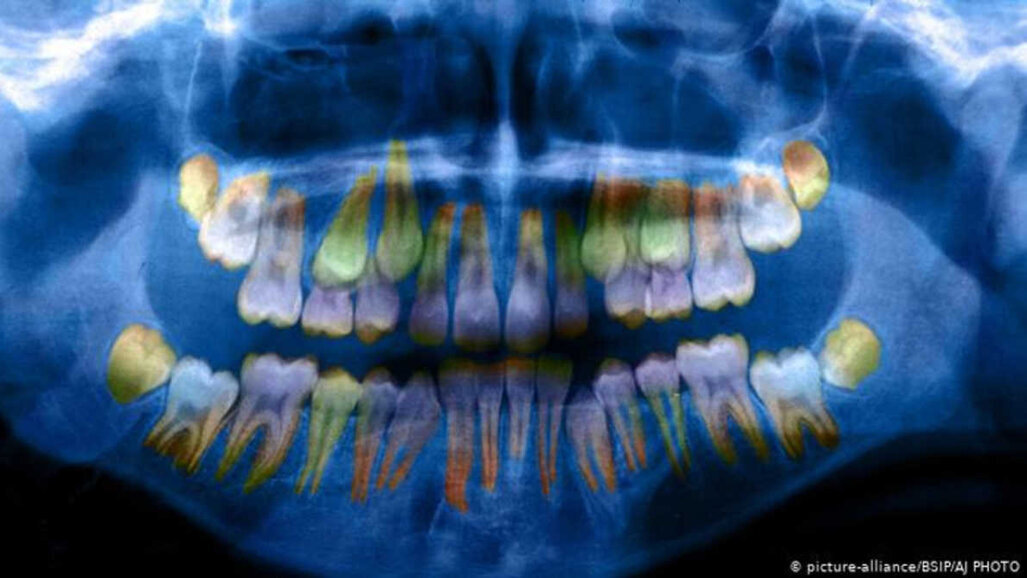

O achado mais importante foi que pode ser observado nos dentes das crianças se elas foram expostas a fatores de estresse elevados em idade precoce. De acordo com o Dr. W. Thomas Boyce, Professor de Pediatria e Pediatria Psiquiatria da Universidade da Califórnia, San Francisco, que apresentou na reunião da AAAS, as camadas individuais que se acumulam no esmalte dos dentes são mais finas e menos densas, se forem expostos ao estresse, o que “aumenta a vulnerabilidade às cáries dentárias”, explicou à emissora internacional alemã Deutsche Welle. Essas alterações podem ser medidas examinando-se um dente primário em um modelo 3-D baseado em uma radiografia.